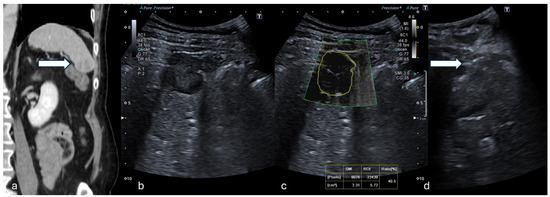

Figure 2.

(a) Axial CT in venous phase shows a hyperdense, vascularized 24 mm solid lesion of the thyroid (white arrow) in a patient who presented with a palpable mass. (b,c) B-mode US showed a dishomogeneous hypo-isoechoic lesion. (d) mSMI and VI analysis providing a value of 31.1%. (e) Percutaneous biopsy using an 18G needle (white arrow). (Histological examination reported a papillary thyroid carcinoma.).